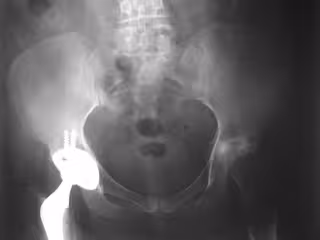

Asocian los días de mayor contaminación con el riesgo de fracturas de cadera

Reemplazo de cadera

Un estudio llevado a cabo por la Universidad Rey Juan Carlos (URJC) sugiere que las condiciones climáticas adversas, y por primera vez, las relacionadas con la contaminación atmosférica podrían ser un factor asociado a las fracturas de cadera osteoporóticas.

"El primero de los estudios describe, por primera vez, la asociación, en el corto plazo, entre niveles elevados de determinados contaminantes (NO2 y SO2) y la incidencia de fractura cadera. De forma que aquellos días con mayor contaminación existe una mayor incidencia de fractura de cadera", según ha explicado el catedrático de Medicina Preventiva y Salud Pública de la URJC Ángel Gil de Miguel.